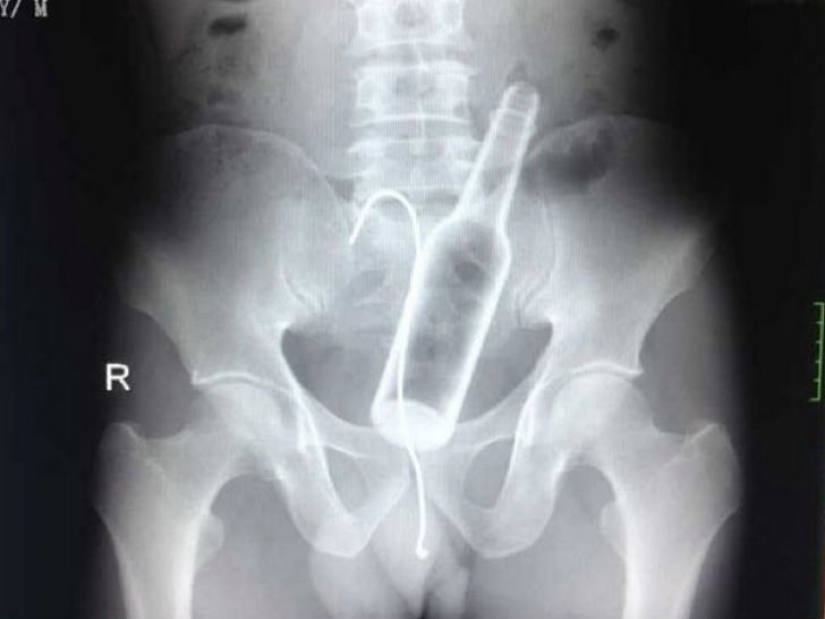

A man came to one of the Chinese hospitals with complaints of abdominal pain. Los médicos tomaron una radiografía y encontraron una botella de vidrio en el estómago.